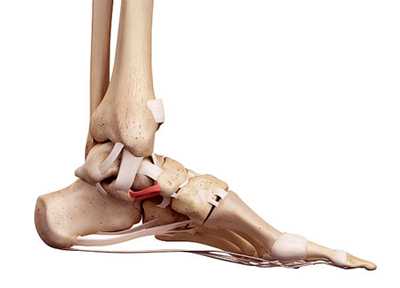

Сустав Шопара укреплен несколькими связками. На тыльной поверхности сустава имеются 4 связки.

- Вилкообразная пяточно-ладьевидно-кубовидная связка состоит из двух частей - пяточно-ладьевидной и пяточно-кубовидной, которые расположены наподобие буквы V. Связка соединяет между собой пяточную, ладьевидную и кубовидную кости, имеет наибольшее значение для удержания этих костей и носит название «ключа» сустава.

- Тыльная пяточно-кубовидная связка расположена более дорзально, чем вилкообразная.

- Длинная пяточно-кубовидная связка расположена более поверхностно, идет от пяточной к кубовидной кости и своими поверхностными волокнами достигает латеральных плюсневых костей.

- Короткая пяточно-кубовидная связка представляет собой широкое образование, которое имеет длину 2 см.

На подошвенной поверхности есть 3 связки.

1. Пяточно-ладьевидная или прыжковая связка. Связка проходит по подошвенной и медиальной поверхности сустава и состоит из верхне-медиальной и нижней связок, которые образуют аппарат, поддерживающий таранную кость по подошвенной поверхности стопы. Связки противостоят смещению головки таранной кости в медиальном и подошвенном направлении, и, т.о. удерживают продольный свод стопы.

2. Верхне-медиальная связка. Пучки волокон перемежается с участками хряща. Эластические волокна отсутствуют. Верхне-медиальная связка вместе с ладьевидной костью и апофизом пяточной кости образует костно-гленоидальную полость. Это полость вогнутой формы, которая охватывает головку таранной кости. Во время физической нагрузки под давлением таранной кости полость деформируется. При этом связка не растягивается и сохраняет свою длину. Верхне-медиальная связка вплетается в дельтовидную связку голеностопного сустава. Вместе обе связки соединяются с сухожилием задней большеберцовой мышцы. Связки обладают практически одинаковыми механическими свойствами.

3. Нижняя связка. Нижняя связка расположена под верхне-медиальной связкой. Она растягивается под давлением со стороны таранной кости.